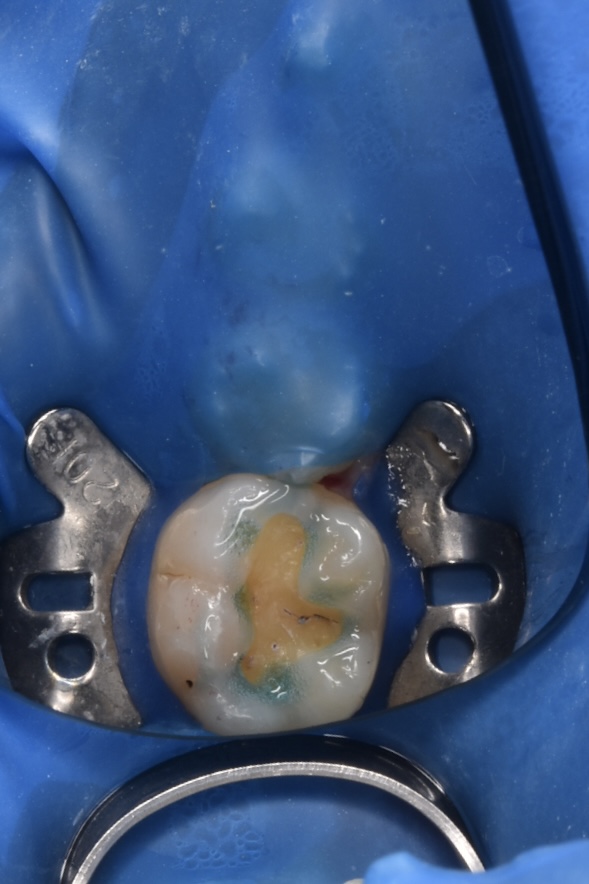

治療プロセス(自由診療のみ適応しているものもあります)